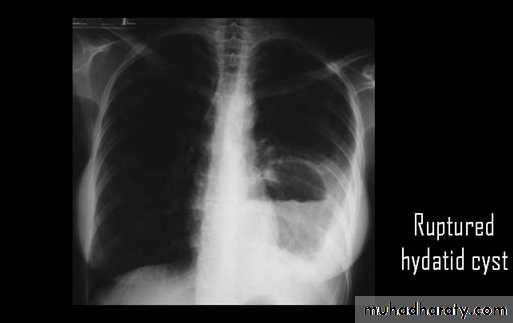

Ruptured hydatid cyst (water lily sign)

Ruptured H.C. With water lily sign .

Un complicated Hydatid cyst of th lung , cuased by echenococus granulosis seen as well defined nodule or mass lesion .

Early rupture is sen as a cresnt air sign .ddx aspergillus ball